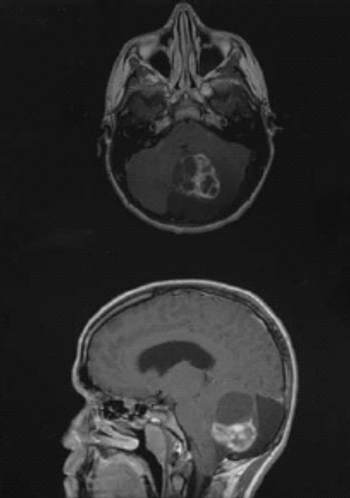

A core set of symptoms are common across brain tumor patients and underscore the complexity of brain tumors and their management.

Depressive symptoms and impaired executive functioning, both common in patients with glioblastoma, are independently associated with shorter overall survival.

The immunotherapeutic rindopepimut with bevacizumab yielded a significant survival improvement in relapsed glioblastoma patients with a EGFRvIII mutation.

A phase I trial of an oncolytic polio/rhinovirus vaccine was safe and showed promising efficacy in patients with recurrent glioblastoma.

Treating newly diagnosed glioblastoma with “tumor treating fields” is a safe and effective therapeutic option, according to a new trial.

A combination of bevacizumab and lomustine showed promise in a randomized phase II trial of patients with recurrent glioblastoma, according to study results.

The addition of procarbazine, CCNU, and vincristine to RT in patients with low-grade glioma prolongs progression-free and overall survival vs RT alone.